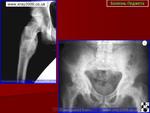

Доснять и таз, и череп, и легкие. От жадности). Педжет/мтс.

Метастазы, смешанного характера, с преобладанием бластического компонента. Не Педжет

Мне кажется, в структуре тазовых костей и бедер преобладает остеосклероз (он метастатический?), на фоне которого видны остеолитические очаги.

Значительный об'ем поражения костной ткани,при чем равномерый и наличие скудных жалоб, при таких mts больная должна иметь анамнез и явную клинику (т.е. уже умирать). Я склоняюсь к Педжету.

Однозначно - тотальное мтс-поражение костей скелета. В анамнезе наверняка рак молочной железы.

Я склоняюсь к Педжету.